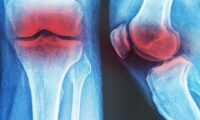

さらに、Scientific Reportsに掲載された別の研究では、ミニマルシューズを6カ月間毎日履くことで、足の指を曲げる力(趾屈力)が強くなったことが分かりました。足の筋力が弱いと、指の変形につながる可能性があります。例えば、「ハンマートゥ」は足の指の中間関節が下向きに曲がってしまう症状で、歩行時の痛みや靴の圧迫による不快感を引き起こします。また「外反母趾」は親指が他の指の方向へ曲がり、関節が突出することで炎症や痛みが生じることがあります。さらに、「クロートゥ」は足の指が縮こまるように丸まってしまい、指の付け根に過剰な圧力がかかることで、靴ずれや歩行時の違和感を引き起こすことがあります。